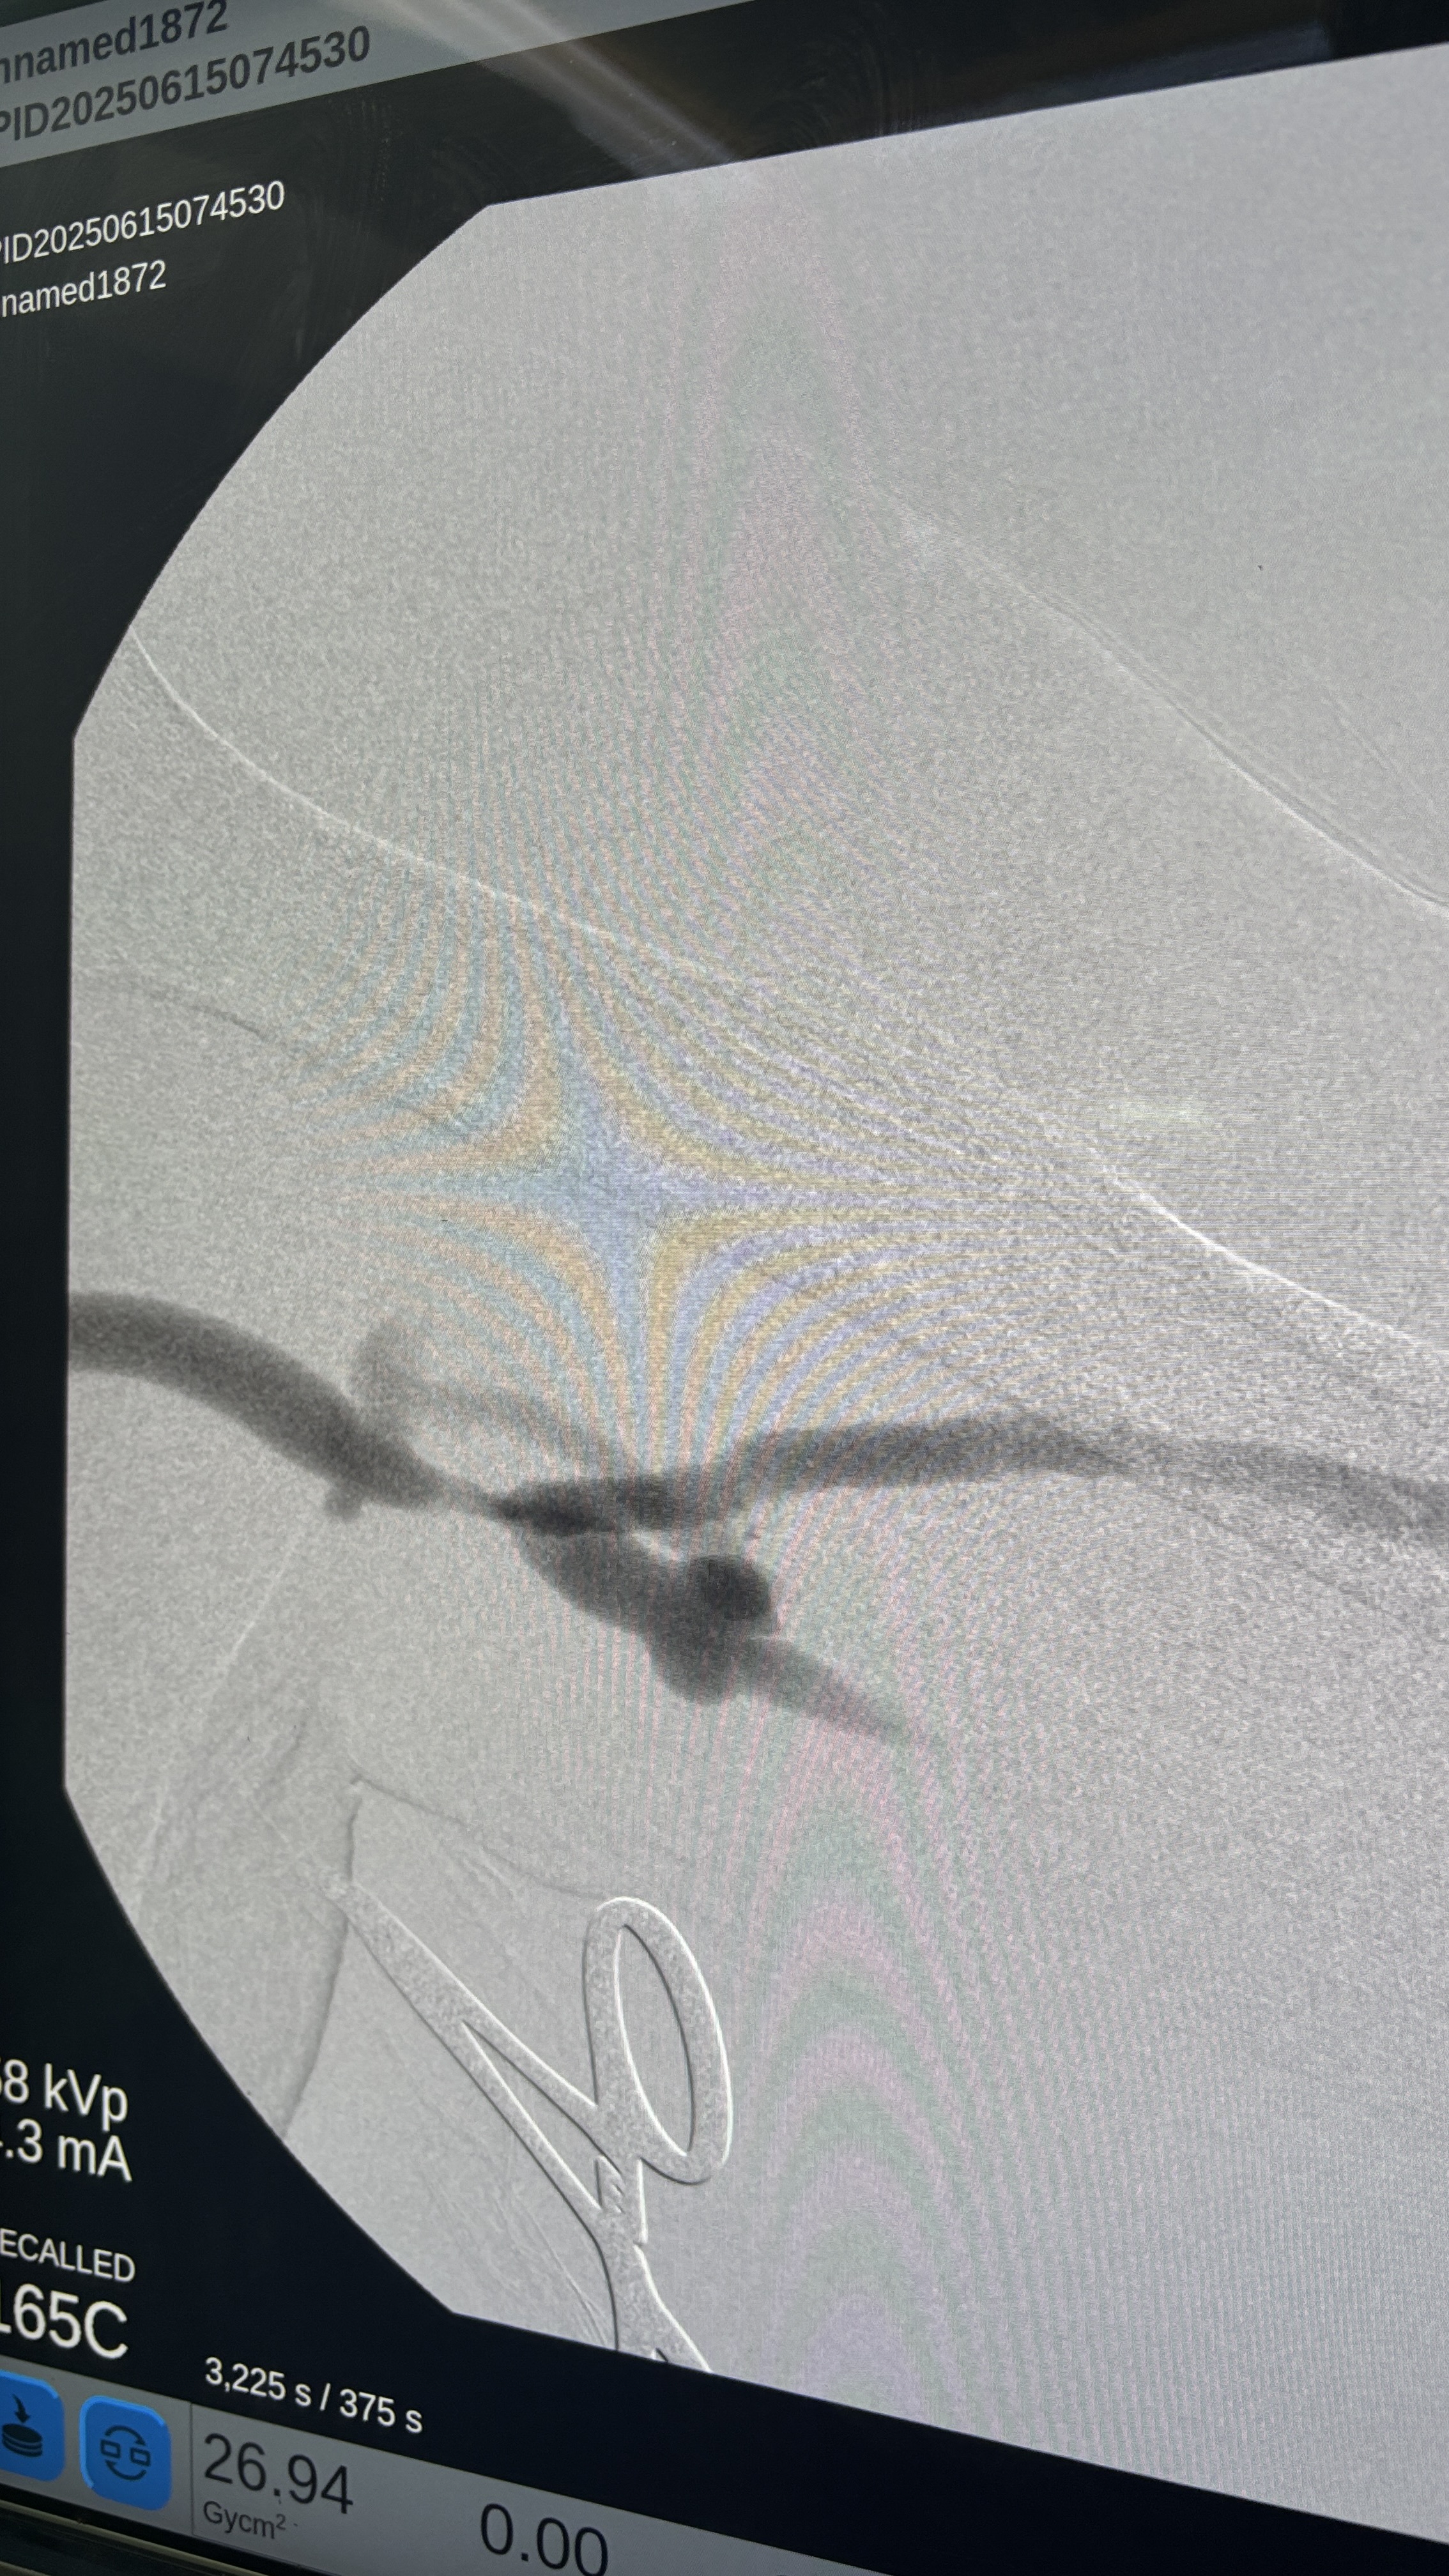

下午開了一個Thrombectomy + PTA,是個可愛的阿公,雖然一直問我刀是要開完了沒,不過開完刀露出來的笑容還真是可愛,讓我想到我自己的阿公,我握著他的手跟他說保重,就跟我之前會跟阿公說的一樣